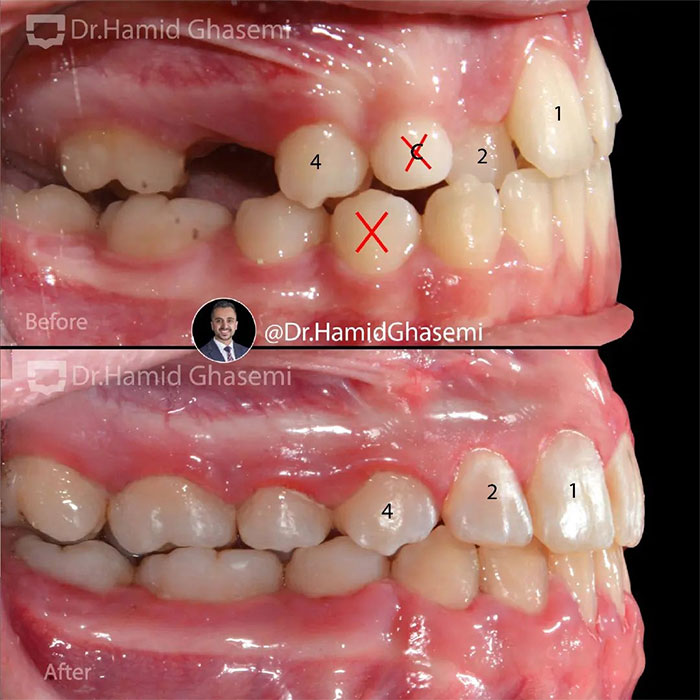

یک کیس خیلی جالب با مشکل جلوزدگی متوسط فک بالا و پایین (Bimaxillary dentoalveolar protrusion ) همراه با نهفتگی دوطرفه دندانهای نیش فک بالا. درمان با کشیدن دندان های نیش نهفته فک بالا و دندانهای پرمولر اول پایین انجام شد. تغییرات مثبت و قابل توجه در پروفایل و حالت لبهای بیمار پس از درمان و کسب اکلوژن کلاس ۱ ایده آل همچنان که دندانهای پرمولر اول بالا جایگزین دندانهای نیش نهفته در فک بالا شدند کاملا مشهود است.

This was such an amazing case with moderate bimaxillary dentoalveolar protrusion plus impacted bilateral upper canines. The case was treated by extraction of upper impacted canines and lower 1st premolars. Significant profile change achieved while upper 1st premolars substituted for upper canines properly with a solid perfect class 1 dental occlusion.